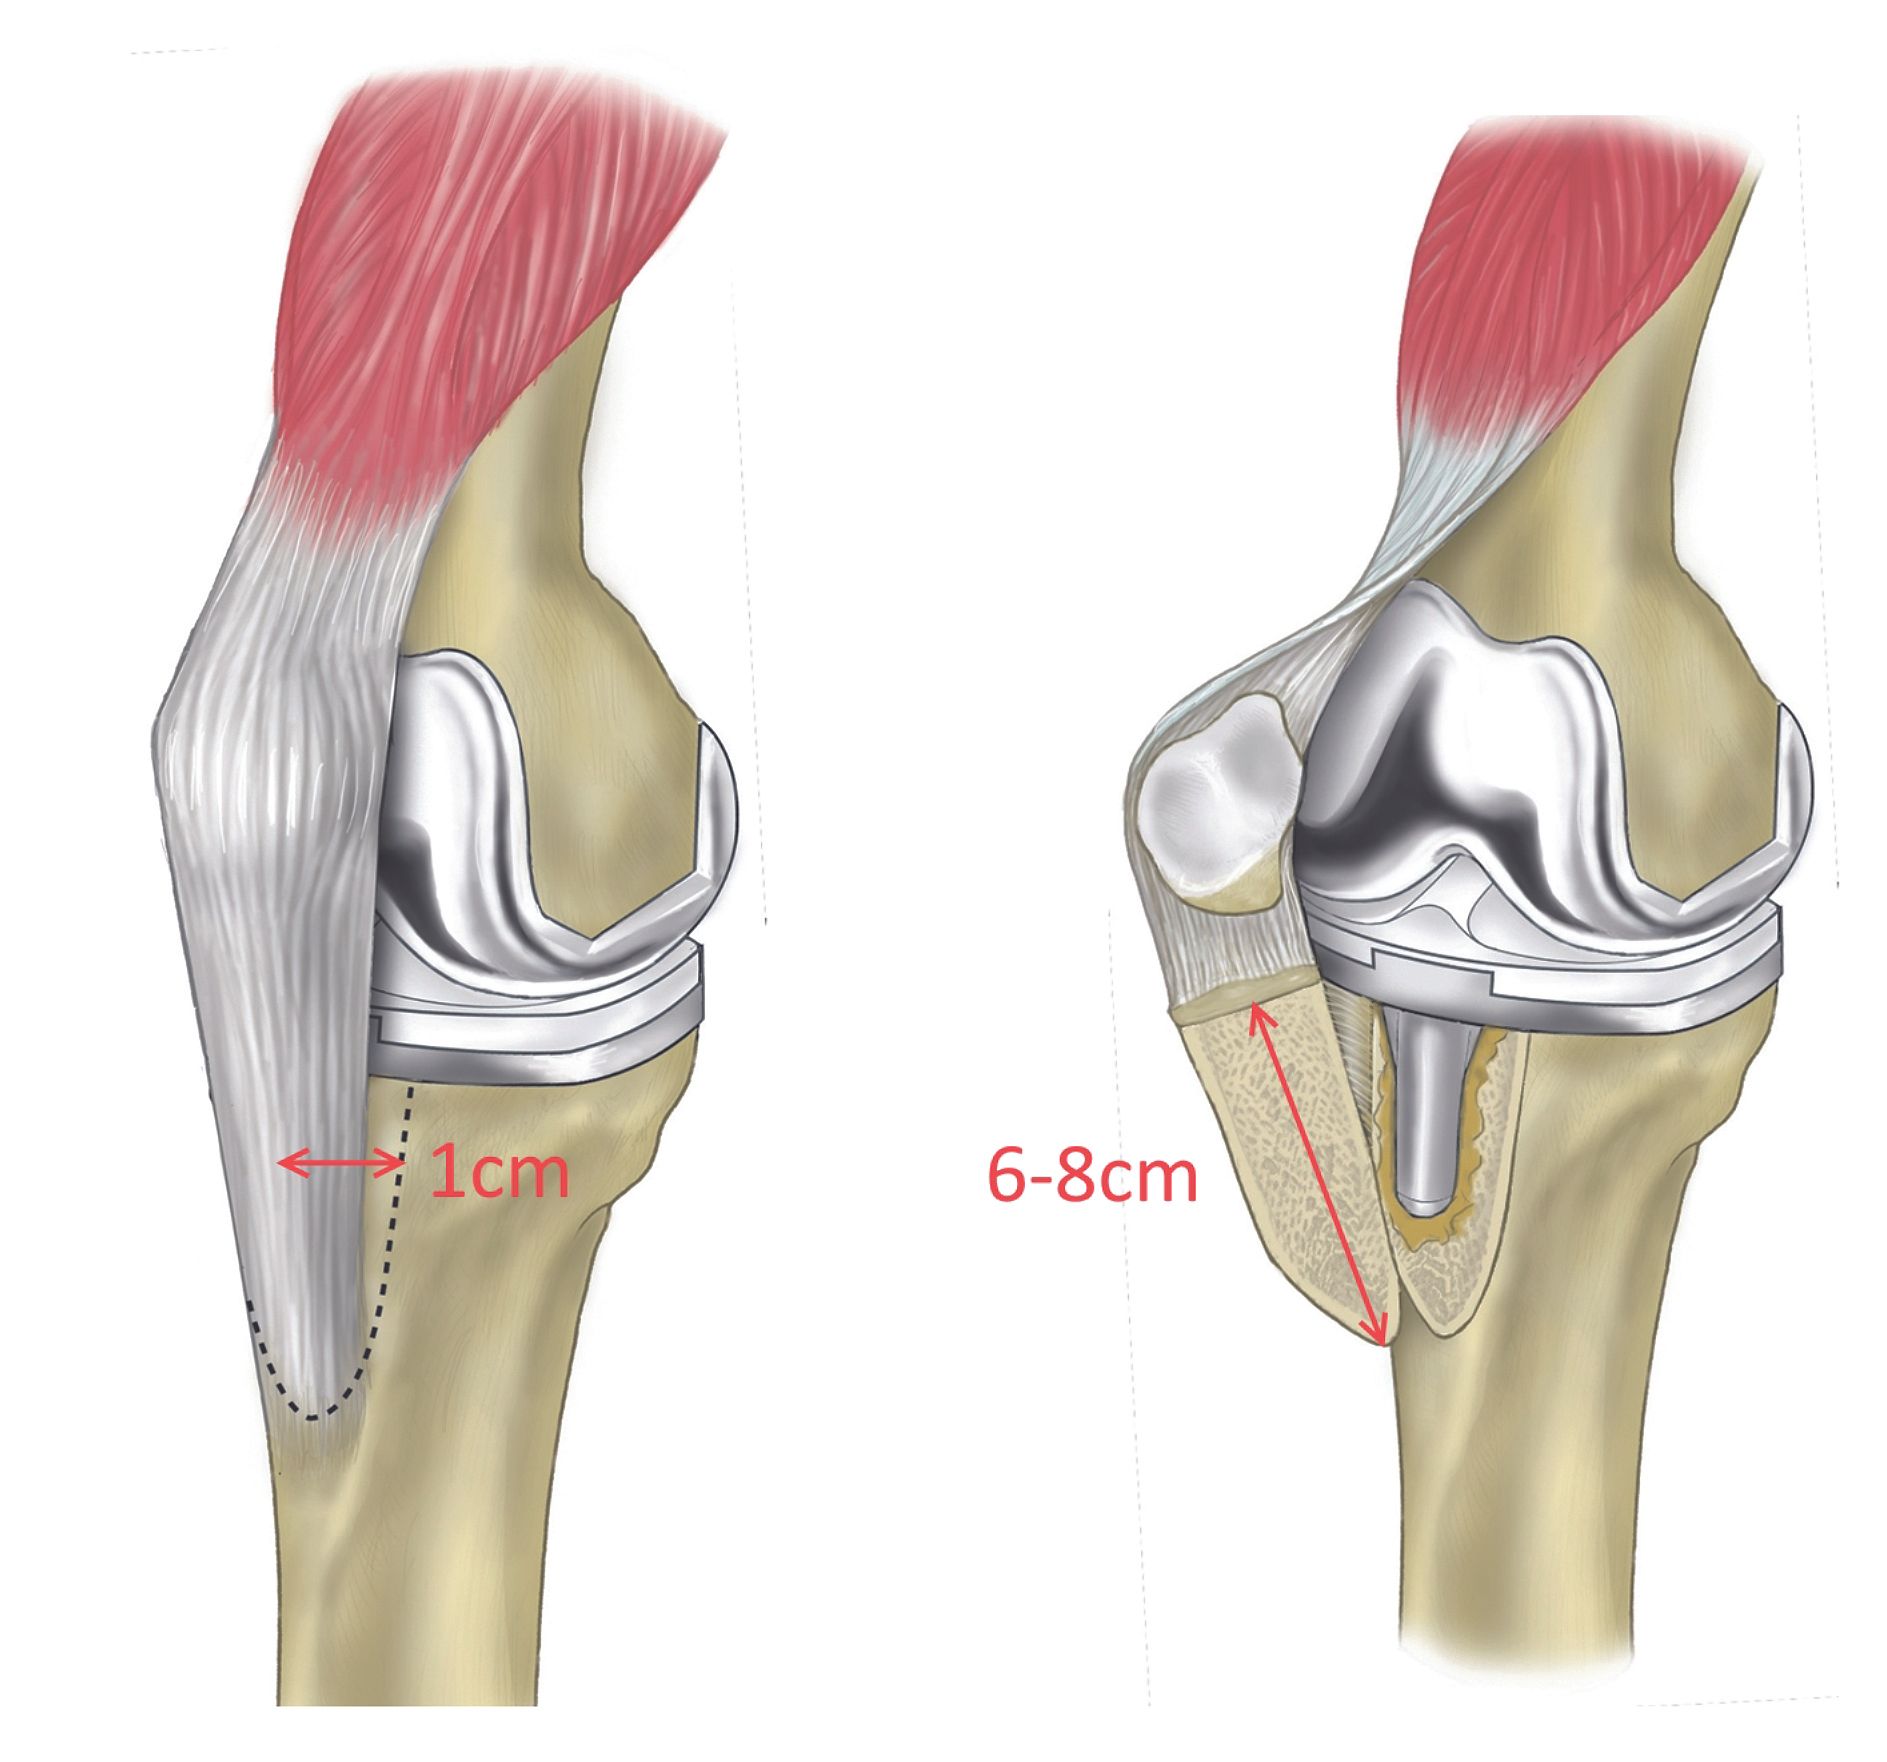

A medial parapatellar approach is undertaken. The retinaculum is incised from the apex of the quadriceps tendon to the tibial tubercle. The synovium is debrided. At this stage, the early decision to perform a TCO is taken if patella is not everting or if access is required to tibial component (via the medulla) for explantation or to the posterior knee for debridement. Place the knee in extension in neutral rotation. The crest is defined medially with subperiosteal dissection. If desired the osteotomy line can be marked out using the electrocautery or a surgical marker pen (figure 1).

Firstly, perform a vertical medial cortical osteotomy. Insert the first sharp broad osteotome from superiorly to inferiorly at the level of the anterior lip of the implanted tibial tray in the coronal plane parallel to the floor creating a maximum thickness of approximately 1 cm, aiming to keep the osteotomy between 6-8 cm in length. Care is taken to include the whole insertion of patella tendon. The osteotome is continued until the anterior tibial cortex distally is reached. This osteotome only engages the medial cortex and some of cancellous bone. Depending on the morphology of the tubercle the osteotomy may need to be ‘bevelled’ obliquely anteriorly at the end to avoid excessive distal propagation- often times this is required in a patient with marked fixed flexion deformity. No proximal or distal steps in the cut are required. Remove this osteotome.

Secondly, perform a horizontal osteotomy (figure 2). Now from the medial side of the tubercle, in a lateral direction insert a sharp broad osteotome superiorly and possibly a second and third osteotome inferiorly adjacent to each other in the osteotomy site carefully impacting and engaging the lateral (far cortex) but no more- the periosteum and lateral structures are to be preserved. The osteotomes are kept in position.